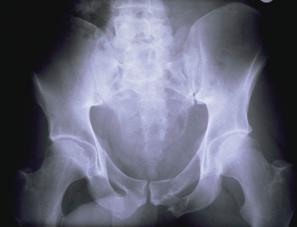

Banda de stabilizare Dallas Fractura de bazin. Radiografie in

incidenta AP

Inaintea

aplicarii benzii de stabilizare Dallas

Fractura de bazin

. Radiografie in incidenta AP Fractura de spina

Dupa aplicarea benzii de stabilizare Dallas prin avulsie. - Stabila -